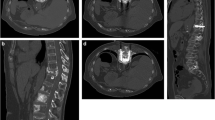

For extensive osteolysis with or without fracture involving more than just the acetabular roof, percutaneous consolidative techniques will have limited results for consolidation (Fig. 8). In particular, lesions that destroy both the cortical bone of the roof and the medial wall of the acetabulum expose the patient to a very high risk of mechanical failure and protrusion of the femur inside the pelvis [1, 43, 44]. Surgery should therefore always be considered in those cases. If the patient is not a surgical candidate, percutaneous cementoplasty +/− screw fixation and thermal ablation might be used for palliation with reserved expectations for stabilization outcomes (Fig. 9) [2, 48].

Cementoplasty for extensive supra-acetabular osteolysis. A Axial CT scan shows a large amount of osteolysis and destruction of the acetabular roof with minimal cortical integrity (asterisk). B Sagittal oblique view shows a diffuse extension of the lesion. The roof of the acetabulum (dotted line) is at high risk of mechanical failure, while the posterior part (black asterisk) has very limited weight-bearing function. C, D The roof was filled as much as possible with cement, while the posterior part was left untreated. Small asymptomatic anterior leakage in the soft tissue. E Axial CT scan in another patient demonstrating a large supra-acetabular osteolytic lesion (asterisk) with destruction of the lateral cortex (arrow). F Axial CT scan more caudally shows that the medial wall of the acetabulum (asterisks) is also completely destroyed. G Large volume cementoplasty was performed as the patient was not a surgical candidate due to other comorbidities. H One-year follow-up shows recalcification under systemic treatment. However, there is a complete destruction of the hip joint due with acetabular protrusion

Combined screw fixation and cementoplasty to consolidate a complex acetabular pathological fracture. A Coronal oblique and B sagittal oblique CT scan show a displaced pathological fracture of the acetabulum, in a patient not eligible for surgery. C AP fluoro-projection and D sagittal oblique CT scan: cementoplasty was performed to reinforce the acetabular roof (asterisk) in combination with one retrograde trans-pubic screw (black arrow) and two anterior trans-iliac screws (white arrow) for fracture fixation. Partial mechanical improvement was noted after the intervention